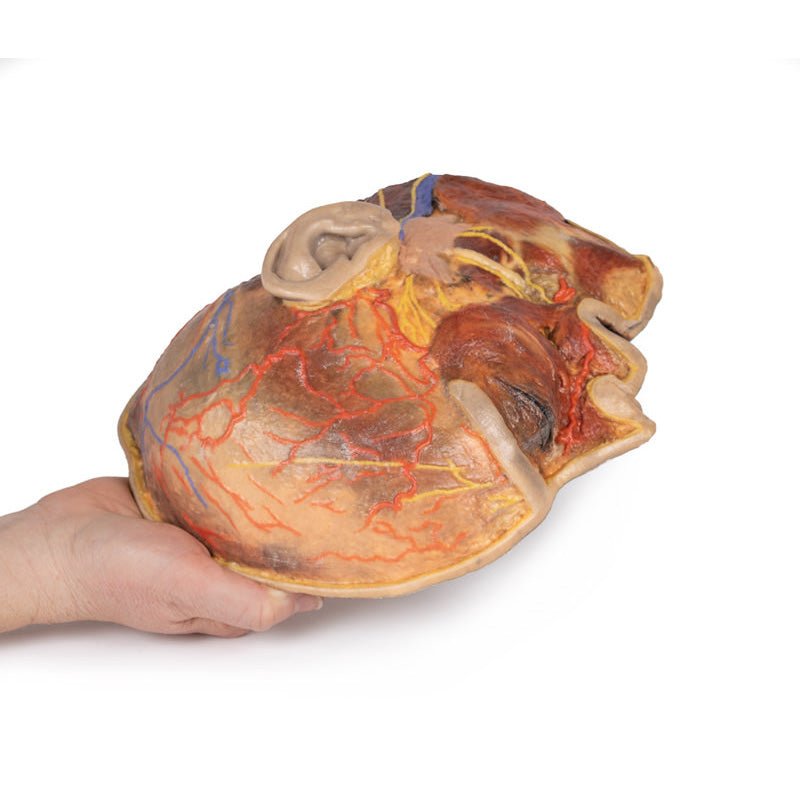

3D Printed Superficial Facial Nerves & Parotid Gland

This 3D model presents the superficial anatomy of the face and head, and compliments the superficial facial anatomy

of our HW 44 model with a more expanded dissection across the scalp and occipital regions.

The superficial

neurovascular and muscular structures in the face largely mirror the structures described in reference to our HW 44

specimen (see description), although the terminal branches of the facial nerve (CNVII) can be largely followed

across a longer course from the parotid gland and the platysma muscle has been retained superficial to the mandible

and extends towards the neck.

In contrast to the HW 44 specimen, this model has a more expansive superficial

dissection inferior to the external ear and across the posterior scalp and occipital region. This allows for an

expanded appreciation of the neurovascular distribution of the supraorbital and supratrochlear nerves and arties

with the superficial temporal artery. Inferior to the ear, the retromandibular vein has been exposed with the

ascending fibres of the great auricular nerve on its superficial surface (and further branches of this nerve on the

surface of the sternocleidomastoid muscle). At the posterior border of the sternocleidomastoid muscle the lesser

occipital nerve is just preserved, near the exiting and ascension of the occipital artery and vein near the

trapezius muscle towards the posterior scalp. Surrounding the external ear are fibres of the auricularis superior

and posterior muscles. Near the margin of the dissection window posteriorly the deep fibres of the occiptalis muscle

can be seen integrated into the epicranius (occipitofrontalis) muscle.